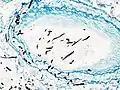

On microscopy, Aspergillus species are reliably demonstrated by silver stains, e.g., Gridley stain or Gomori methenamine-silver.[27] These give the fungal walls a gray-black colour. The hyphae of Aspergillus species range in diameter from 2.5 to 4.5 μm. They have septate hyphae,[28] but these are not always apparent, and in such cases they may be mistaken for Zygomycota.[27] Aspergillus hyphae tend to have dichotomous branching that is progressive and primarily at acute angles of around 45°.[27]

Pulmonary invasive aspergillosis in a person with interstitial pneumonia (autopsy material), using Grocott's methenamine silver stain